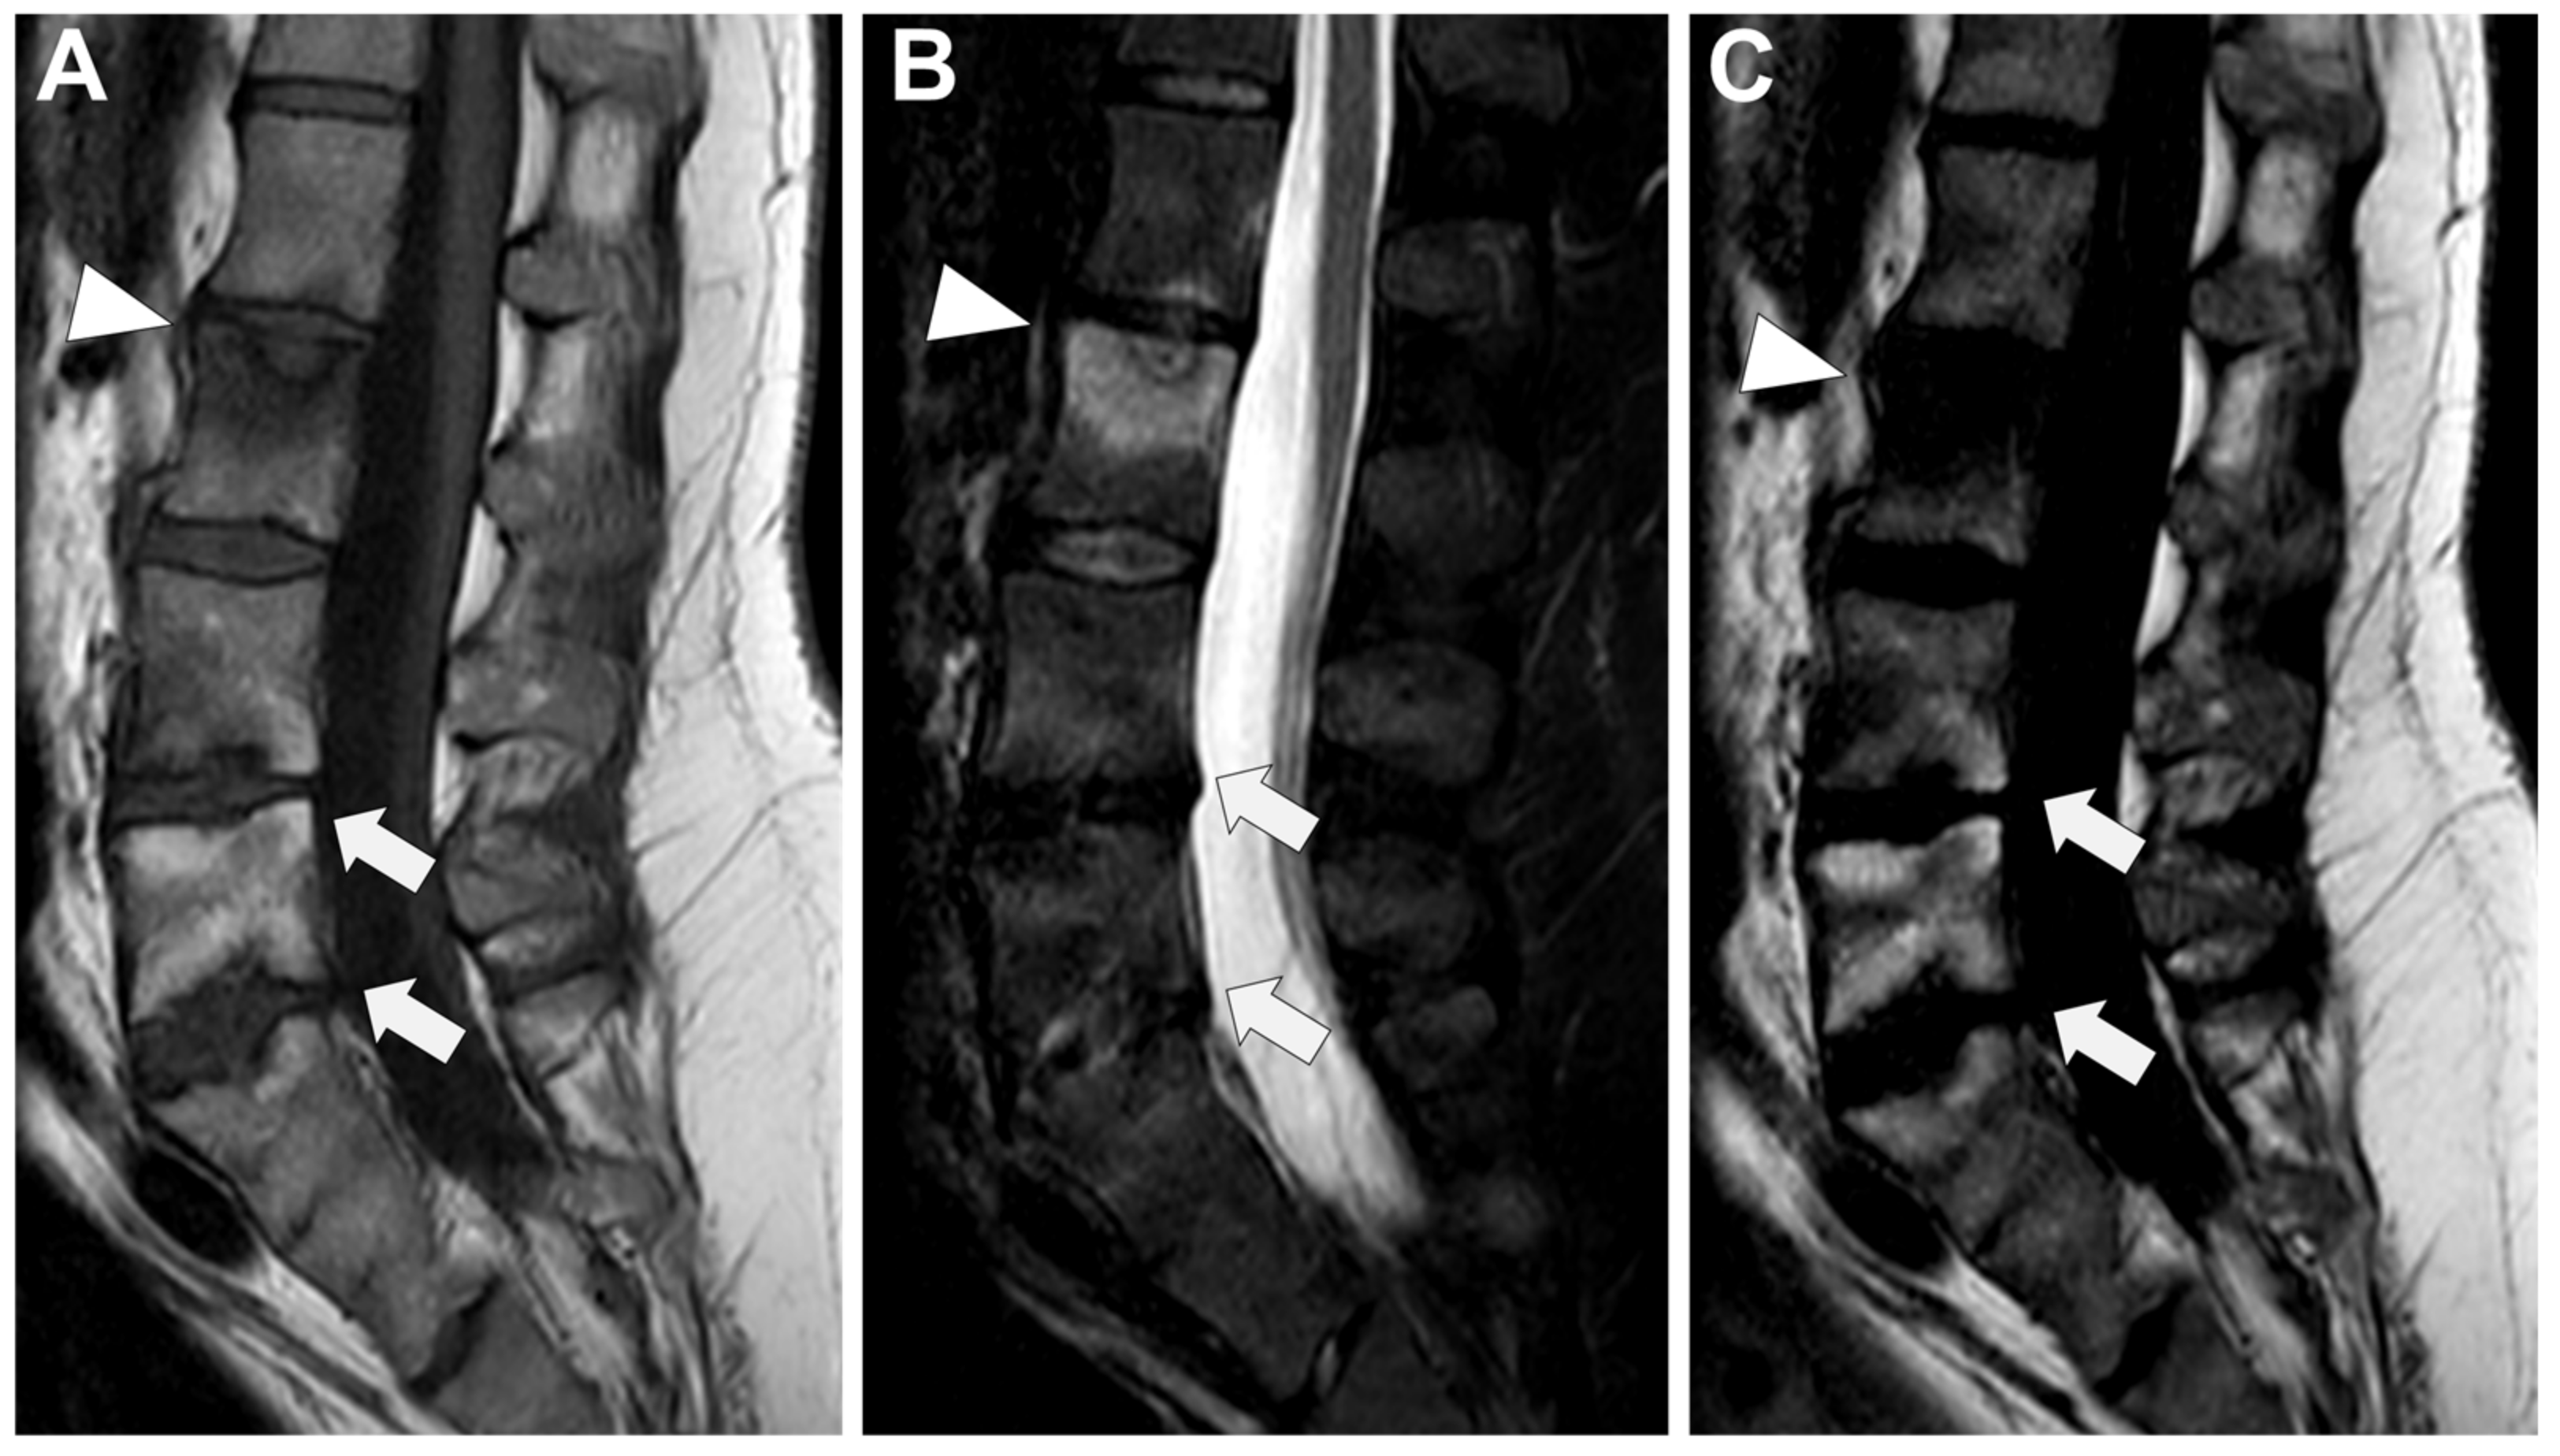

In Figure 6 an exemplificative case of TbS is presented.

Figure 6. Tubercular spondylodiscitis. A 24-year-old man of Sudanese origin presented with thoracic and lumbar pain evolving for several months. An MRI was performed with (A) T2-weighted imaging (WI) and (B) contrast-enhanced (CE) T1-WI, as well as a CT-scan in bone kernel (C) and abdominal kernel after contrast medium injection (D,E). It demonstrates preserved disk but extensive sub ligamentous collections spreading along the anterior side of the thoracic and lumbar vertebral bodies (white arrowhead), but also along the posterior vertebral collateral ligament (white arrows) with large anterior and posterior erosions (black arrows). Please note the extensive collections spreading in the presacral space and along bilateral iliopsoas muscles without surrounding inflammation (white dashed arrows).